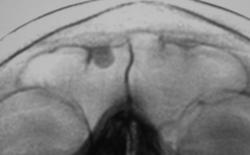

Иллюстрации 3, 4, 5, 6. Варианты скиалогической картины лобной пазухи «с увеличением изображения»

При анализе иллюстраций 3, 4, 5, 6 чётко дифференцируется неоднородность тени остеомы за счет очаговых уплотнений.